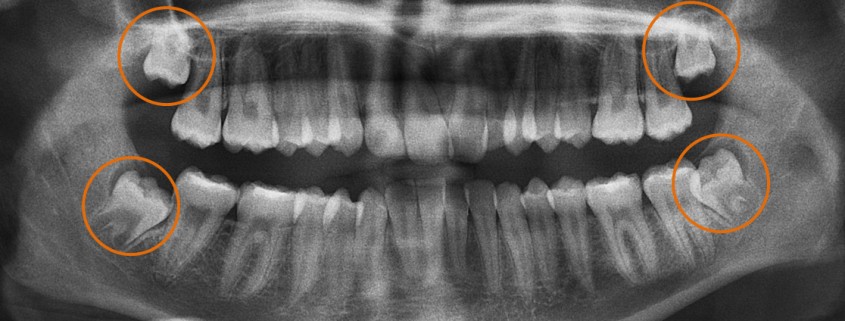

Revisión completa de tus terceros molares, encías y estructura ósea para determinar su estado actual.

Evaluación y diagnóstico preciso: analizamos y te detallamos exactamente el paso a paso de todo tu tratamiento.